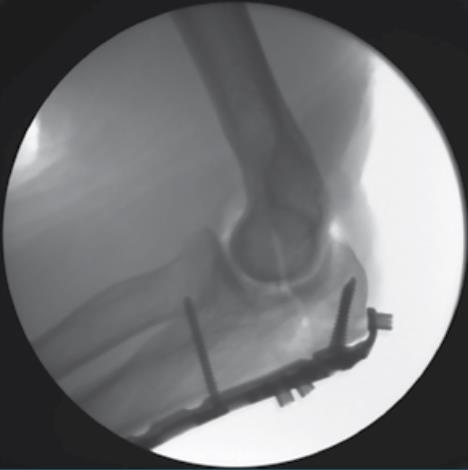

• Over Drilling the Home Run Tab

• using the T-10 Driver, remove the PDG in the HR tab

• drill up to the fracture line using the 3.5mm drill bit

• fluoroscopic imaging is helpful during this step

• Lagging the Proximal Fragment

• loosen the screw previously placed in the oblong hole of the shaft

• insert the recorded length 3.5mm Multi-Threaded Compression Screw through the HR tab to further reduce the fracture

• retighten the screw in the oblong hole of the shaft

• Fluoroscopic Confirmation

• confirm proper plate positioning, fracture reduction and screw lengths using fluoroscopic imaging